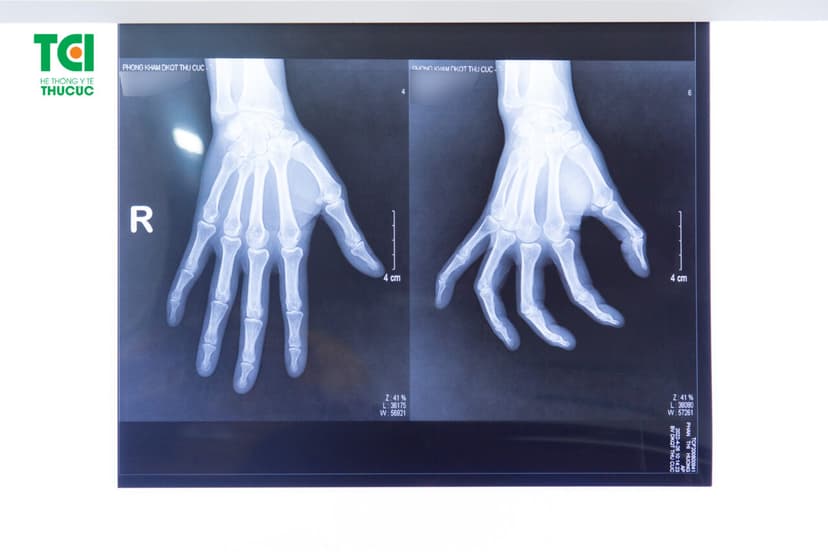

Sau đó, bác sĩ sẽ chỉ định người bệnh thực hiện kỹ thuật chẩn đoán hình ảnh thông qua chụp X-quang. Phương pháp này nhằm xem xét những dấu hiệu viêm khớp ngón tay, các cựa xương, sụn hay khoảng trống của khớp…

Chụp X-quang giúp chẩn đoán chính xác tình trạng viêm